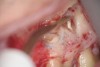

Clinical procedure: Once a perforation occurs, the extent of the perforation must be assessed. If there is an adjacent bony defect, the bony defect should first be filled with an osteoconductive or osteoinductive material. This can be done with a bone graft, calcium sulfate, or collagen/gelatin sponge. The dentinal portion of the tooth that has been perforated is then restored with MTA (Figure 9 through Figure 14).

Fig 9 Preoperative radiographs showing mesial perforation.

Figure 9

Fig 10. Preoperative radiographs showing mesial perforation.

Figure 10